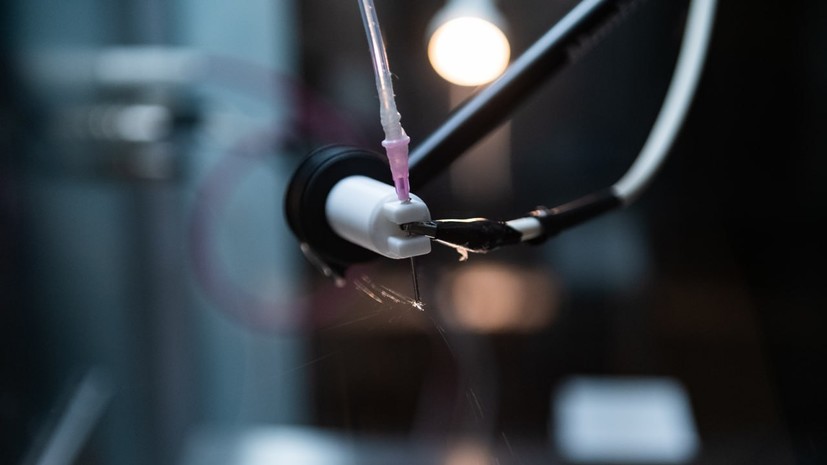

- Нейроимплант, разработанный учёными НИТУ МИСИС

- © Пресс-служа НИТУ МИСИС

Учёные НИТУ МИСИС разработали нейроимплантат для восстановления спинного мозга после повреждения. Имплантат, который планируется вживлять в место травмы, состоит из биосовместимых полимеров и имеет особую структуру, которая обеспечивает направленный рост нервных тканей человека. Об этом RT сообщили в пресс-службе МИСИС.

Авторы исследования создали новые материалы для имплантатов такого типа — наноструктурированные каркасы, состоящие из резорбируемого полимера.

«Мы используем биорастворимые полимеры, которые близки по механическим характеристикам к нативным тканям спинного мозга. Была создана направленная наноструктура, на которую клетки прикрепляются и продолжают свой путь вдоль конструкции, как по рельсам», — рассказала RT сотрудник научно-образовательной лаборатории тканевой инженерии и регенеративной медицины НИТУ МИСИС Элеонора Зеленова.

Имплантаты планируется вживлять в место травмы. По словам учёных, их разработка уже доказала свою эффективность в лабораторных экспериментах на клеточных культурах. Сейчас проводятся испытания на животных.